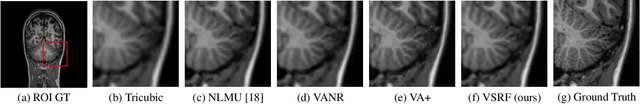

Abstract:Magnetic resonance imaging (MRI) enables 3-D imaging of anatomical structures. However, the acquisition of MR volumes with high spatial resolution leads to long scan times. To this end, we propose volumetric super-resolution forests (VSRF) to enhance MRI resolution retrospectively. Our method learns a locally linear mapping between low-resolution and high-resolution volumetric image patches by employing random forest regression. We customize features suitable for volumetric MRI to train the random forest and propose a median tree ensemble for robust regression. VSRF outperforms state-of-the-art example-based super-resolution in term of image quality and efficiency for model training and inference in different MRI datasets. It is also superior to unsupervised methods with just a handful or even a single volume to assemble training data.